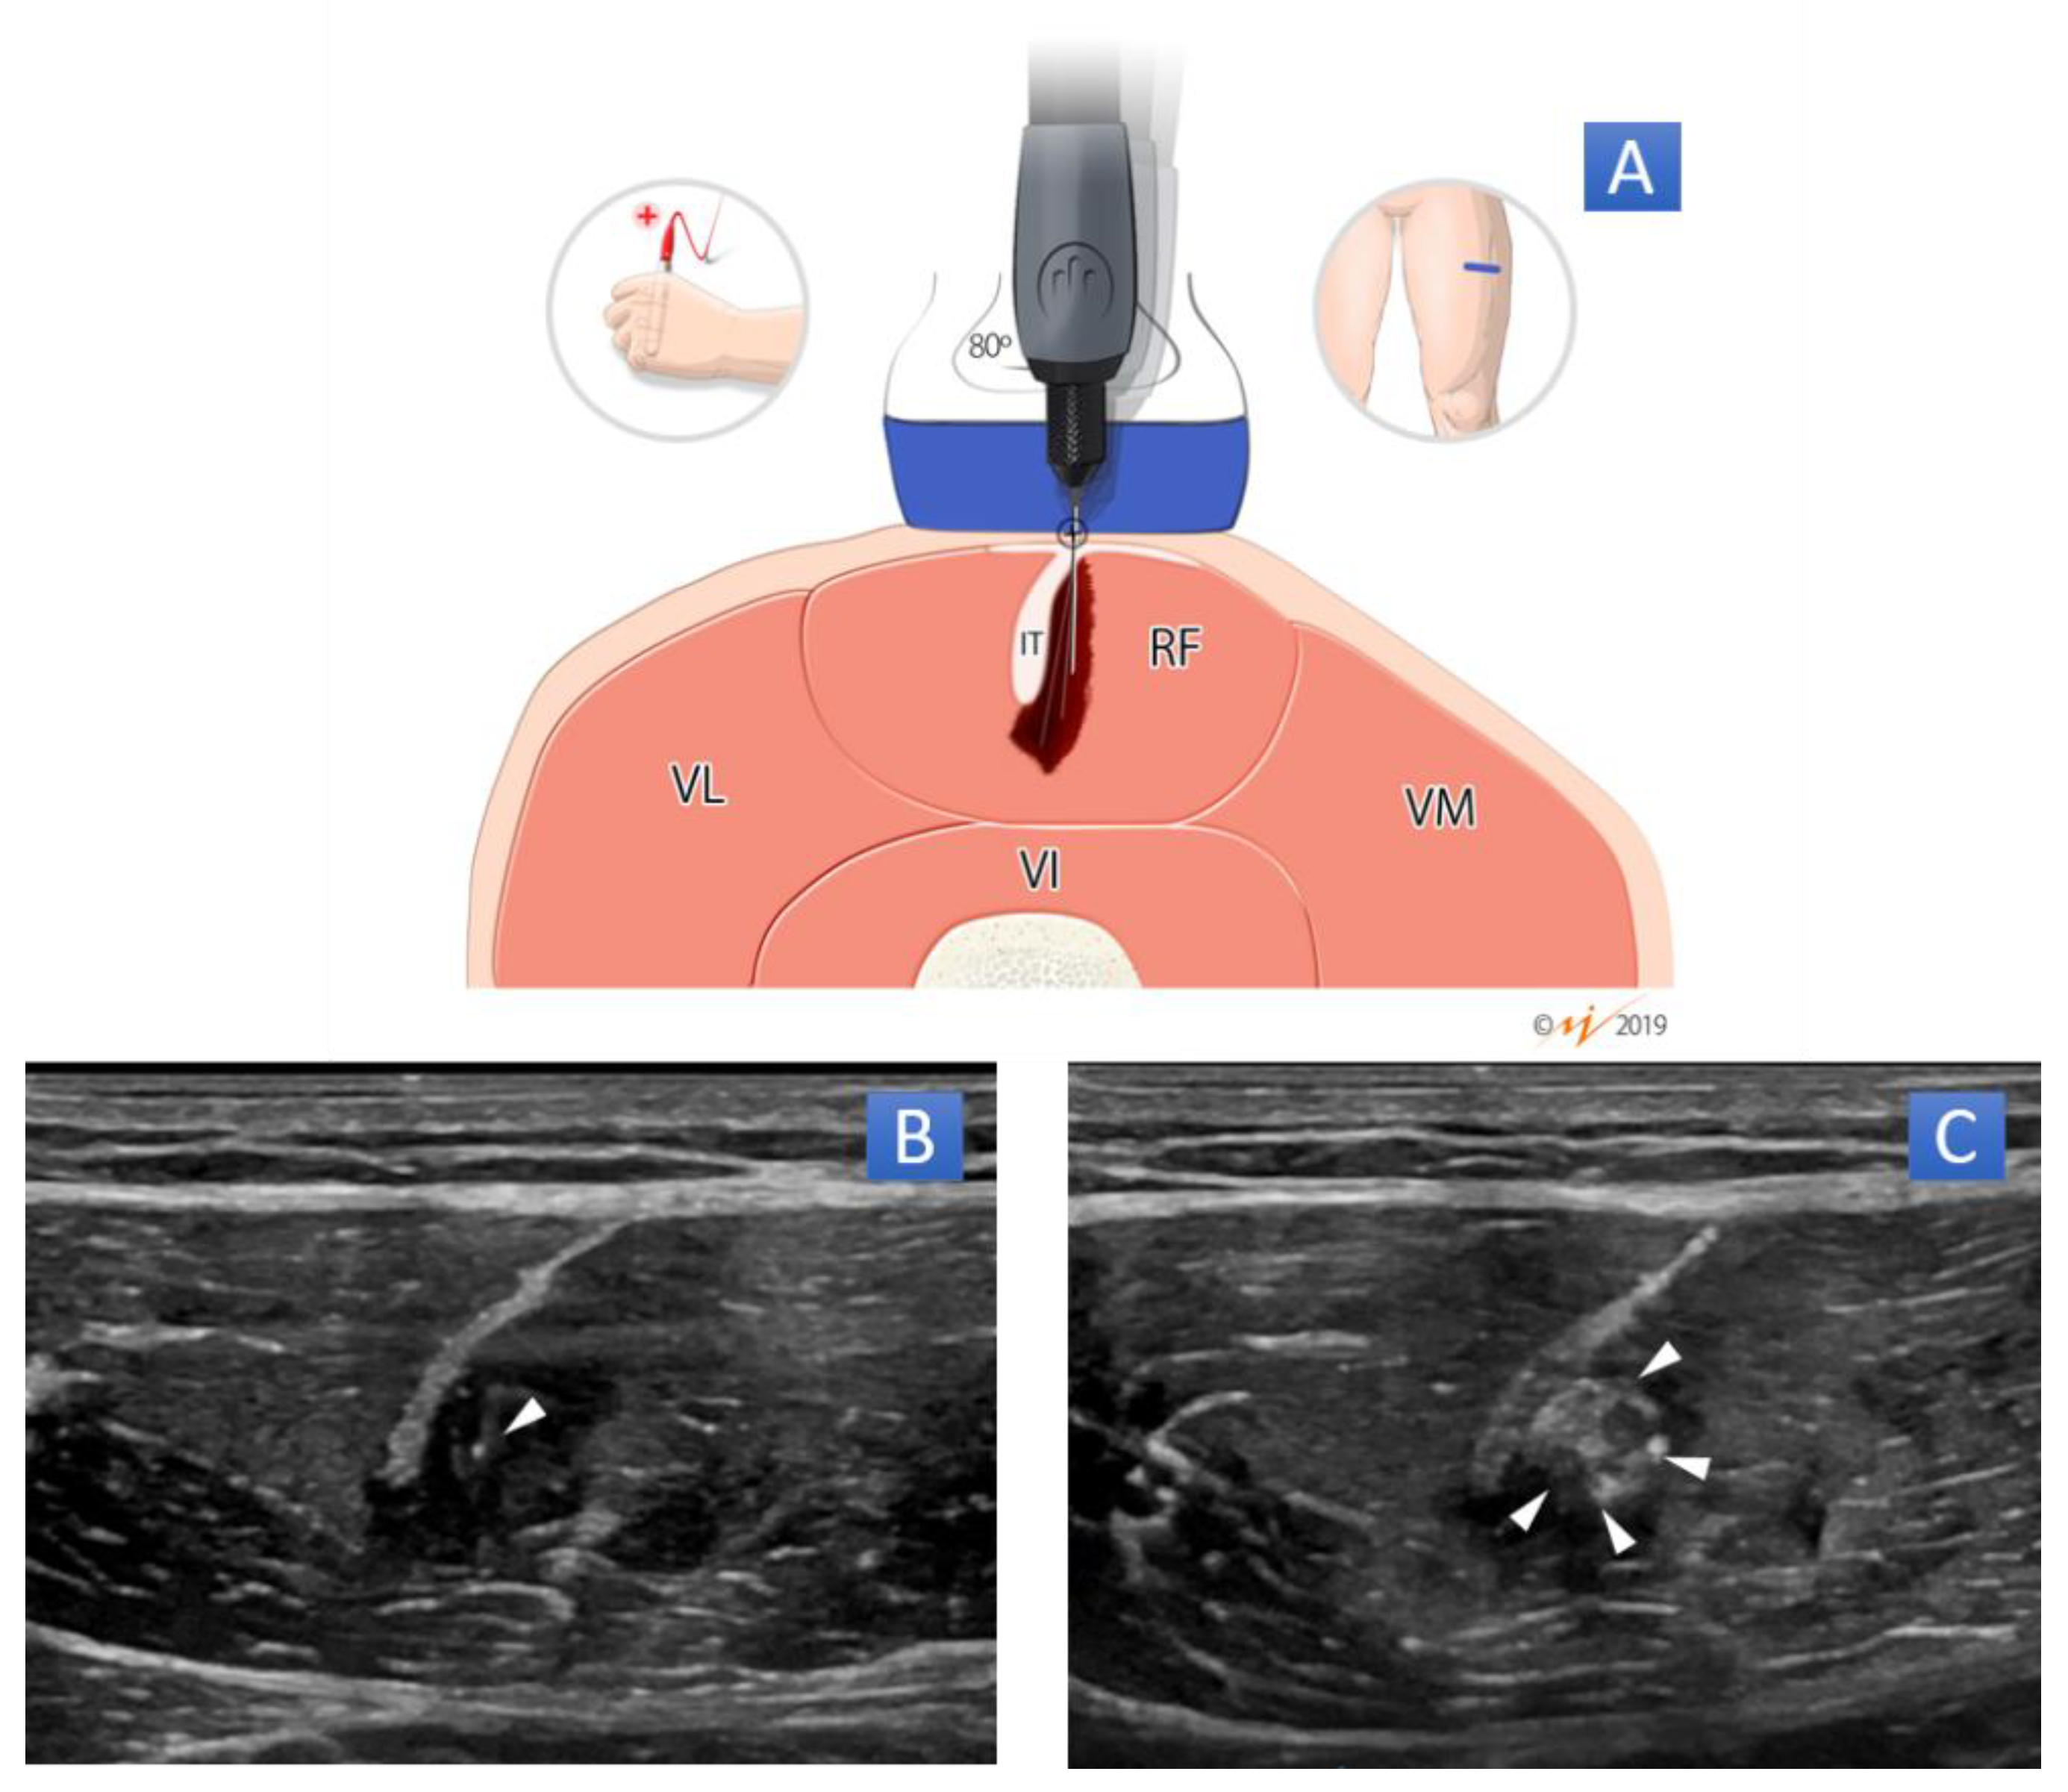

Figure 2.

Percutaneous needle electrolysis (PNE) technique for rectus femoris muscle injury. (A) Graphic scheme in transverse plane. Short-axis approach at an 80-degree angle into the area of muscle injury (dark red part). (B) B-mode ultrasound image of PNE technique in which arrowhead represents the tip of the needle in a short-axis approach in area of muscle injury. (C) B-mode ultrasound image of PNE technique in which the white area represents the hydrogen gas released during the electrolysis. RF: rectus femoris; VM: vastus medialis; VL: vastus lateralis; VI: vastus intermedius; IT: intramuscular tendon of RF muscle.